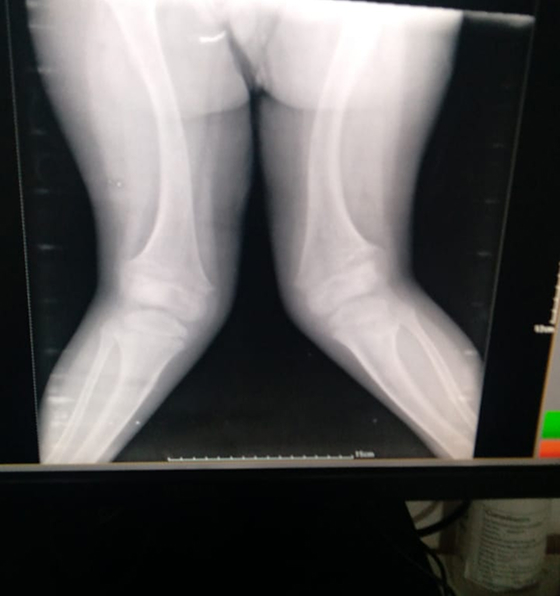

Caring for Growing Knees

Knee issues are common in children, ranging from sports injuries to growth-related alignment problems like knock-knees or bow legs. Early treatment prevents future pain and deformity.

We provide:

- Treatment for ligament injuries and meniscus tears

- Non-surgical care for alignment concerns

- Surgical correction for severe deformities

- Sports medicine for active children and teens

“From playground tumbles to sports injuries, every knee tells a story, we make sure it heals the right way.”